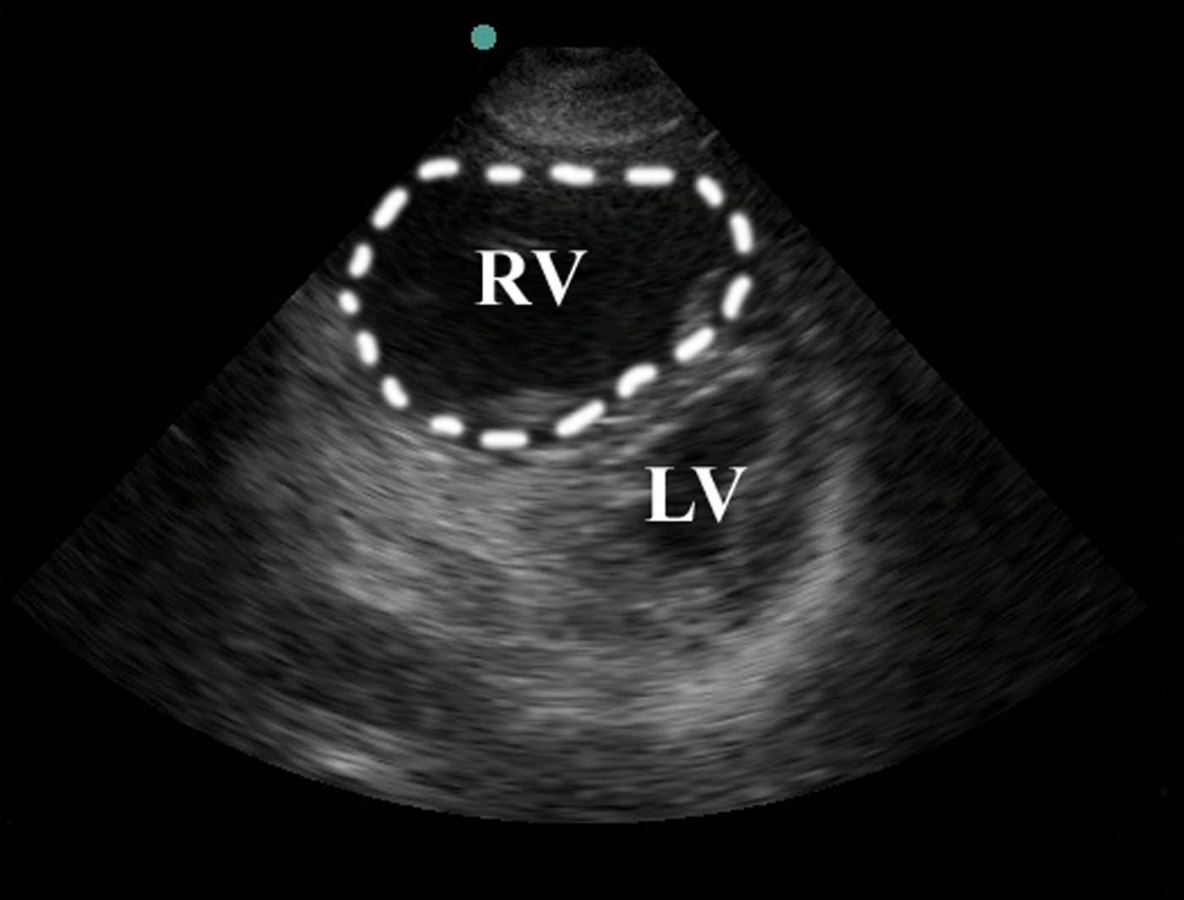

The test of choice for ED evaluation is bedside echo. Although the definitive test for diagnosis of pulmonary HTN with resultant right heart failure is a right heart catheterization, this is unrealistic in the ER setting. On a bedside transthoracic echo, there are certain findings that point the differential towards right heart failure. The first is right ventricular enlargement. Right ventricular enlargement is defined as the right ventricle being greater than two-thirds the size of the LV. Basically if the RV looks the same size or greater than the LV, worry about some sort of RV overload. Another important finding is flattening of the interventricular septum, which is identified by a D-shaped LV when using the parasternal short axis view. The IVC should also be assessed and as a plethoric IVC without variation can point towards increased RV pressure or possibly failure. Other signs of RV failure include tricuspid regurgitation as well as decreased RV contractility.